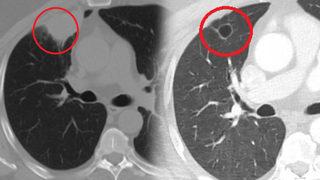

Dünya tıp literatüründe bir ilk! Koronavirüs akciğer kanserini taklit etti

Kahramanmaraş'ta akciğer kanseri teşhisi konulan N.T.'nin koronavirüs testi pozitif çıktı. Ameliyat öncesi koronavirüs tedavisi gören N.T.'ye yapılan tetkikler sonucu koronavirüsün akciğer kanserini taklit ettiği tespit edildi. Sütçü İmam Üniversitesi Sağlık Uygulama ve Araştırma Hastanesi Göğüs Cerrahi Ana Bilim Dalı Öğretim Üyesi Dr. Fatoş Kozanlı, koronavirüsün akciğer kanserini taklit ettiğini ve bunun dünya tıp literatüründe bir ilk olduğunu söyledi.